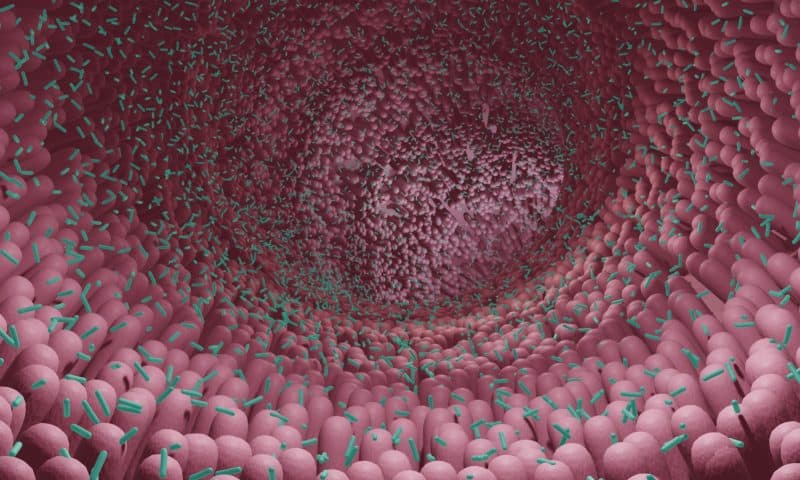

GlycoCaging is a chemical process inspired by the UBC researchers’ realization that certain molecules found in fruit and vegetable fiber can only be digested by bacteria that reside in our gut. “Using molecular insights into dietary fiber metabolism by the human gut microbiota, we designed a targeted drug delivery system based on bespoke glycoconjugates of a complex plant oligosaccharide called GlycoCaging,” they explained. The team bonded the molecule to a steroid, creating a “treasure chest” for which the “key” is a specific gut bacteria.

They reasoned that the hydrophilic, branched oligosaccharide should prevent premature absorption in the upper GI tract, but support targeted release of the drug, resulting from the activity of specific xyloglucanases produced by colonic microbiota. “Building upon our knowledge of microbiota enzyme specificity, we hypothesized that covalent conjugation of small-molecule drugs to a singular xyloglucan heptasaccharide via a glycosidic linkage could make a molecular platform for GI targeting …” the investigators further stated.